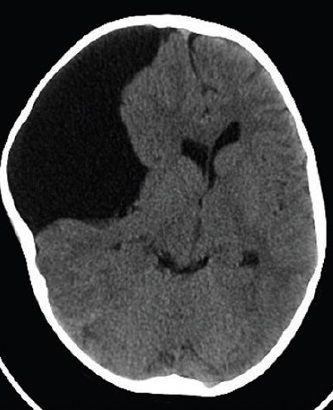

2. Hemorragias

1. Por ruptura de vasos arteriales y anomalias vasculares como aneurismas o malformaciones arteriovenosas.

1. La hemorragia se difunde con rapidez por el espacio subaracnoideo y produce aumento de la presion intracraneal con cefalea, vómitos y alteraciones del Edo de conciencia.

1. El tejido que sufre privación sanguinea experimenta infarto o necrosis isquemica (zona de ablandamiento o encefalomalacia)

1. Se produce daño local al parenquima cerebral con afección funcional de dicha zona

1. Edema Unilateral